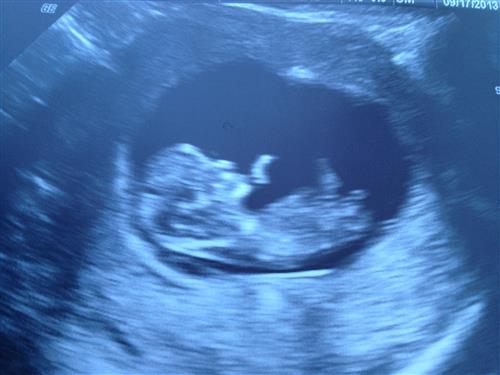

Baby #2

10w2d